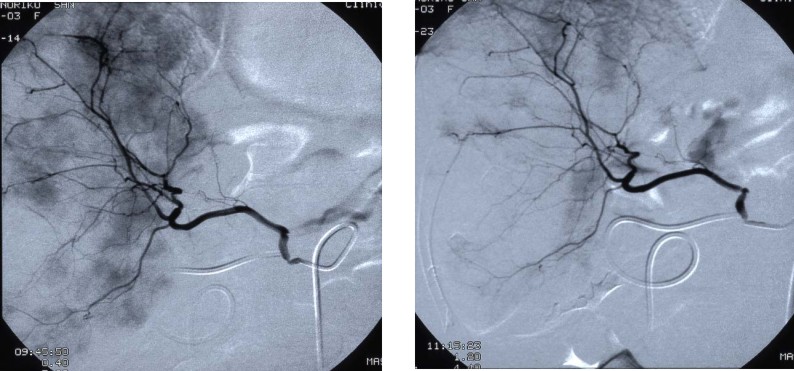

病例2 乳腺癌肝转移

A 治疗前DSA示肝内广泛瘤染色 B 微血管介入治疗后立刻造影示染色早明显减少

C 治疗前MRI示肝内广泛病灶 D 治疗3月病灶减少